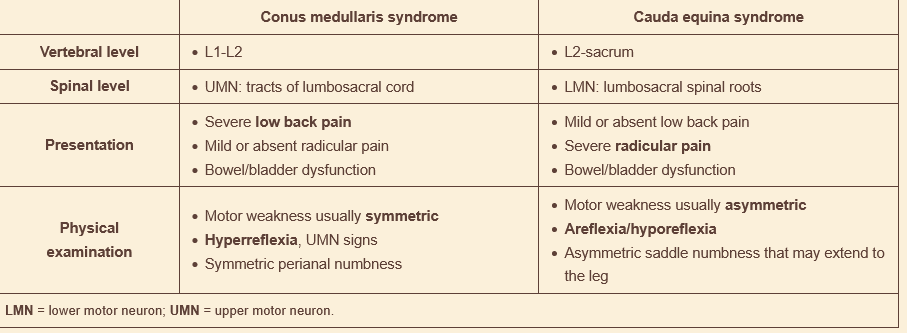

conus medullaris syndrome vs cauda aquina syndrome